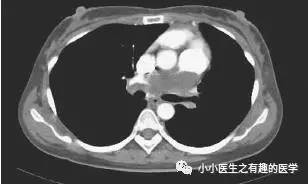

这是什么?妥妥的肺栓塞啊,还能有啥?

怎么办?肿么办?

别慌,米国人民的治疗和我们一样。

抗凝治疗,2周后,病人呼吸困难加重返院。

He was treated expectantly with anticoagulants for pulmonary embolism but returned 2 weeks later with worsening dyspnea and echocardiographic evidence of right heart failure.

抗凝治疗,病情加重,怎么办?这下该好好想想,肿么办?

行动脉血栓内膜剥脱术,然而,结果示黏液性梭形细胞肉瘤。

Surgical thromboendarterectomy revealed a high-grade myxoid spindle cell sarcoma。

是的,这不是肺栓塞,这是肺动脉内膜肉瘤。这不是扯蛋肺栓塞,这是扯蛋肺动脉肿瘤。扯蛋是肯定的,然而,血栓且不肯定。